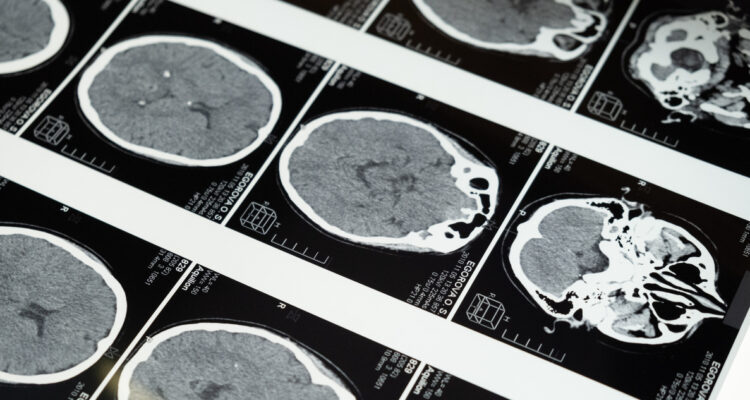

Si solo lees los titulares de la neurociencia sobre el sexo del cerebro, saldrás pensando que el cerebro es masculino o femenino. Pero algunos neurocientíficos sostienen que muchas de las investigaciones neurológicas que han abordado la cuestión del sexo biológico del cerebro en los últimos 30 años no han sido bien realizadas. Aquí examinaremos algunas de ellos.

En primer lugar, todos los neurocientíficos coinciden en que el cerebro masculino es más grande que el femenino. Los científicos dicen que esto se debe a que los cuerpos masculinos son en promedio más grandes que los femeninos.

Pero eso no siempre se ha tomado en cuenta en los estudios que analizan las diferencias entre ambos. Por ejemplo, muchos estudios suelen indicar que la amígdala masculina -que participa en el procesamiento de las emociones asociadas al miedo- es más grande que la femenina.

Pero la investigadora Lise Eliot y su equipo descubrieron que cuando tomaban en cuenta el hecho de que el cerebro femenino era más pequeño que el masculino, casi no había diferencia entre el tamaño de la amígdala femenina y la masculina.

La importancia de considerar el tamaño del cerebro se demostró en un gran estudio de 2018 en el que los investigadores de la Universidad de Edimburgo encontraron que el 85% de las diferencias en los cerebros de hombres y mujeres se volvieron irrelevantes cuando tomaron en cuenta el hecho de que los cerebros masculinos eran más grandes que los femeninos.